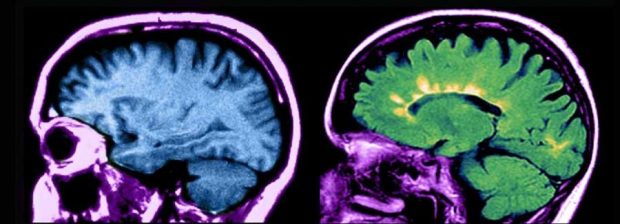

این بیماری باعث میشود که دستگاه ایمنی به رشتههای عصبی مغز و طناب نخاعی حمله کند. اکثر بیماران در دههی ۲۰ و ۳۰ زندگیشان به این بیماری مبتلا میشوند.

وقتی سلول بنیادی وارد بدن بیمار میشود، دستگاه ایمنی دوباره از نو در بدن ساخته میشود. این سلولهای بنیادی از خون خود بیمار برداشت میشوند. چون این سلولها در مرحلهی اولیه هستند، هنوز نقصهایی را که منجر به بیماری ام اس میشود، ندارند.